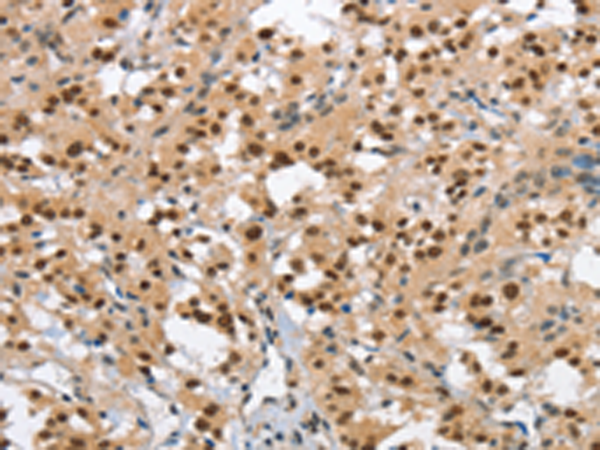

分类: 科研抗体货号: P11596别名: WBS; DIWS; SPIN; IB291; BAP135; BTKAP1; TFII-I; WBSCR6; GTFII-I应用: WB,IHC反应种属: Human, Mouse, Rat